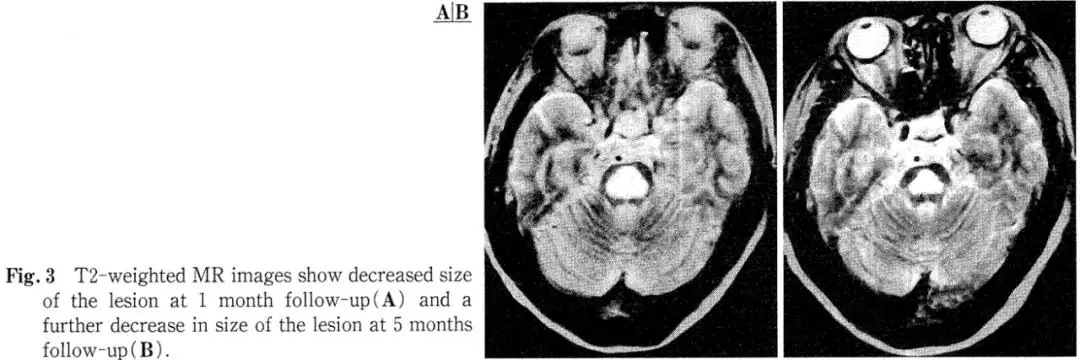

Imaging: A head CT performed at an outside hospital 13 days prior to admission was unremarkable (Fig. 1). However, admission MRI of the brain showed an oval, hypot intense area in the central pons on T1-weighted images, which appeared as a homogeneous hyper-intense lesion on T2-weighted images. This hypot intense area on T1 did not show enhancement after Gadolinium-DTPA administration (Fig. 2A-D). Follow-up MRI at 30 days and 5 months post-admission demonstrated a reduction in lesion size (Fig. 3A, B).

Follow-up: A brain MRI performed one year later showed further significant shrinkage of the pontine lesion (Fig. 4A, B), and neurological examination remained normal.

Conversely, sequential MRI often shows that acute-phase lesions rarely shrink or disappear completely, with most persisting for 6 months to 2 years. Miller et al. reported one case where the pontine abnormality decreased in size after six months, while another showed no change. In our patient, shrinkage was evident on the one-month follow-up MRI, and the lesion was reduced by more than half after one year. Therefore, long-term MRI observation in CPM is considered to reflect acute-phase edema, subacute-phase demyelination, and chronic-phase gliosis, which is crucial for differential diagnosis. From this perspective, CPM's MRI appearance can mimic cerebral infarction, metastatic or glial tumors, multiple sclerosis, encephalitis, and post-chemoradiation changes. Differentiation from tumors is based on the lack of mass effect; from multiple sclerosis by the larger, solitary lesion; and from infarction by the sparing of corticospinal tracts. However, as Kleinschmidt-DeMasters et al. also reported in 8 autopsy-confirmed asymptomatic CPM cases—all featuring small central pontine lesions—and as Koch et al. emphasized, differentiation from infarction can be most challenging, underscoring the importance of clinical context and sequential MRI observation.